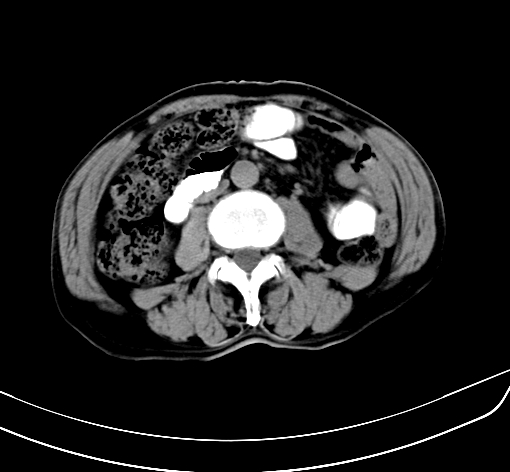

病人 男 70 咳嗽 胃部不适 2月余

胆囊壁增厚,与临近肝实质边界不清,临近肝实质内可见大片边界不清之低密度区,肝门区密度亦有减低,部分结构不清,尾叶前方可见块状影,肝右叶可见多枚边界不清之圆形低密度区,肝内胆管扩张征象,结合病史考虑1胆囊癌肝内转移,肝门区淋巴结转移,门脉癌栓待排2肝内胆管扩张3建议增强扫描

肝脏多发大小不等低密度灶,边界不清,肝门区结构不清,肝内胆管轻度扩张,胆囊密度不均匀,内见软组织样密度影,与相临肝脏边界不清.考虑:1、胆囊ca侵犯肝脏并肝内多发转移,肺上也有结节影,转移?建议强化扫描.2、胃充盈不好,如怀疑有病变最好建议做相关检查.

胆囊壁增厚,周围模糊不清,肝内多发低密度影,胃充盈欠佳,胃壁增厚,外形尚规整,考虑胆囊炎、胆囊癌肝内转移?建议胃肠道进一步检查或增强扫描。